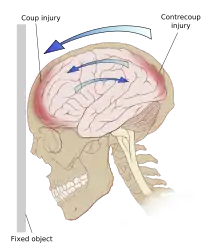

El TCE es causado por fuerzas externas a la cabeza que pueden clasificarse como fuerzas de contacto y de inercia. Las fuerzas de contacto suelen causar lesiones focales como fracturas de cráneo, contusiones y hematomas como el epidurales o subdurales. Cuando la inercia actúa sobre la cabeza causa aceleración por traslación o rotación con o sin una fuerza de contacto. Este es el caso de los «latigazos» que se producen cuando se frena bruscamente un vehículo. Dado que el cerebro no está rígidamente unido al cráneo, el movimiento de traslación por inercia del cerebro en la cavidad craneal puede causar contusiones, hematomas intracerebrales y hematomas subdurales, por impacto de la masa encefálica con las estructuras craneales. La inercia por rotación o angular suele tener un efecto más importante y puede causar daño axonal difuso. Un TCE grave puede ser resultado solamente de fuerzas de aceleración/desaceleración sin daño alguno en el cuero cabelludo.[3][15]

Existen dos tipos de daño primario: el traumatismo craneal cerrado (TCC) y el traumatismo craneal penetrante (TCP). En el TCC el impacto directo del cerebro contra el cráneo y el corte de las estructuras neurovasculares por las fuerzas de rotación o de rebote dan como resultado el daño en el cuerpo celular y los axones. Los accidentes de tráfico son colisiones a alta velocidad muy rápida y son particularmente perjudiciales debido a que las estructuras neuronales, que residen en un compartimento lleno de líquido, se mueven durante la parada repentina del cuerpo en movimiento chocando contra la bóveda craneal. Las estructuras se golpean tanto en el plano directo como en el opuesto del movimiento contra la lámina ósea interna. Esta es la base del patrón de lesión por golpe-contragolpe donde se ve una lesión contusional o en el cerebro profundo que el lugar del impacto del cráneo y 180 grados opuesto al lugar del impacto. Si hay fuerzas de rotación, las estructuras se tuercen y pueden ocurrir desgarre. Esta es la causa de la lesión axonal difusa y se ve comúnmente en TAC o MRI como hemorragias después del TCE[8]

Las contusiones se encuentran en 20% al 25% de los pacientes con TCE grave. Son lesiones heterogéneas compuestas de zonas de hemorragia puntiforme, edema y necrosis que aparecen en las imágenes de TC como áreas de hiperdensidad puntiforme (hemorragias), con hipodensidad circundante (edema), suelen estar localizadas en la cara inferior del lóbulo frontal y la cara anterior del lóbulo temporal por su relación con el ala mayor del esfenoides. También se pueden encontrar en la superficie de impacto y en la superficie contraria a este, el llamado efecto golpe-contragolpe. Cuando estas evolucionan se parecen más a los hematomas intracerebrales y su ubicación depende el posible efecto de masa.